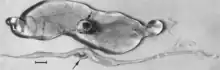

Macroscopic changes of embryos are death followed by resorption of fluids (Fig. 4) and then soft tissues (Fig. 5). Virus and viral antigen are widely distributed in tissues of infected embryos and their placentas,[84] and it is probable that microscopic lesions of necrosis and vascular damage, subsequently described for fetuses, also develop in advanced embryos.